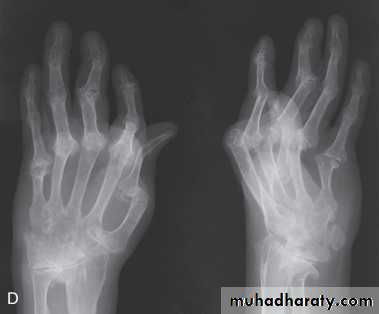

Xrays may be normal or show erosive change with joint space narrowing. Features that favour PsA over RA include the characteristic distribution of proliferative erosions with marked new bone formation, absence of periarticular osteoporosis and osteosclerosis.

Imaging of the axial skeleton often reveals features similar to those in chronic reactive arthritis, with coarse, asymmetrical, nonmarginal syndesmophytes and asymmetrical sacroiliitis.